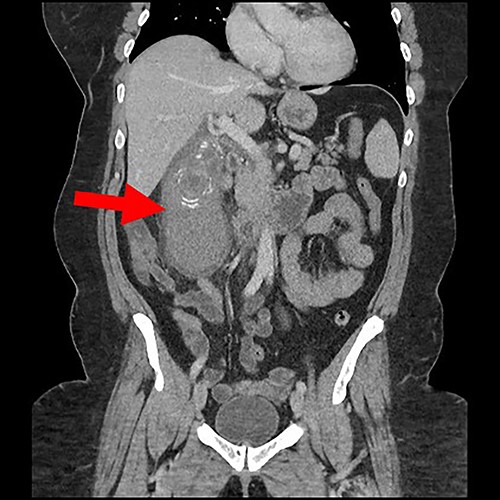

Coronal view of gall bladder with high-density fluid and calculi.